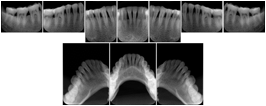

3. A dental provider wishes to capture a series of DICOM IO images for the patient’s dentition. The tooth morphology, teeth are divided into molars, premolars, canines and incisors, and a number of images for each jaw. The anatomic information was captured utilizing the triplet of schema. This standard code sequence is based on ISO 3950-2010, Dentistry - Designation system for teeth and areas of the oral cavity.

Every IO image should have anatomic information either through the primary or modifier sequence.

In most standard cases, images are oriented in structured layouts. These structured displays are useful to be shared between providers for reference purposes.

Table OO.1.1-1 shows structured display standard templates, where Viewset ID is based on the Japanese Society for Oral and Maxillofacial Radiology (JSOMR) classification provided by JIRA (Japan Medical Imaging and Radiological Systems Industries Association, www.jira-net.or.jp). Expected or typical teeth to be imaged location, region and designation codes are based on ISO 3950-2010, Dentistry - Designation system for teeth and areas of the oral cavity. For all the hanging protocols listed in OO.1.1-1, the value to use for Hanging Protocol Creator (0072,0008) is "JSOMR" and the value to use for Hanging Protocol Name (0072,0002) does not include "JSOMR" (e.g., "DL-S001A", not "JSOMR DL-S001A").

Table OO.1.1-1. Hanging Protocol Names for Dental Image Layout based on JSOMR classification